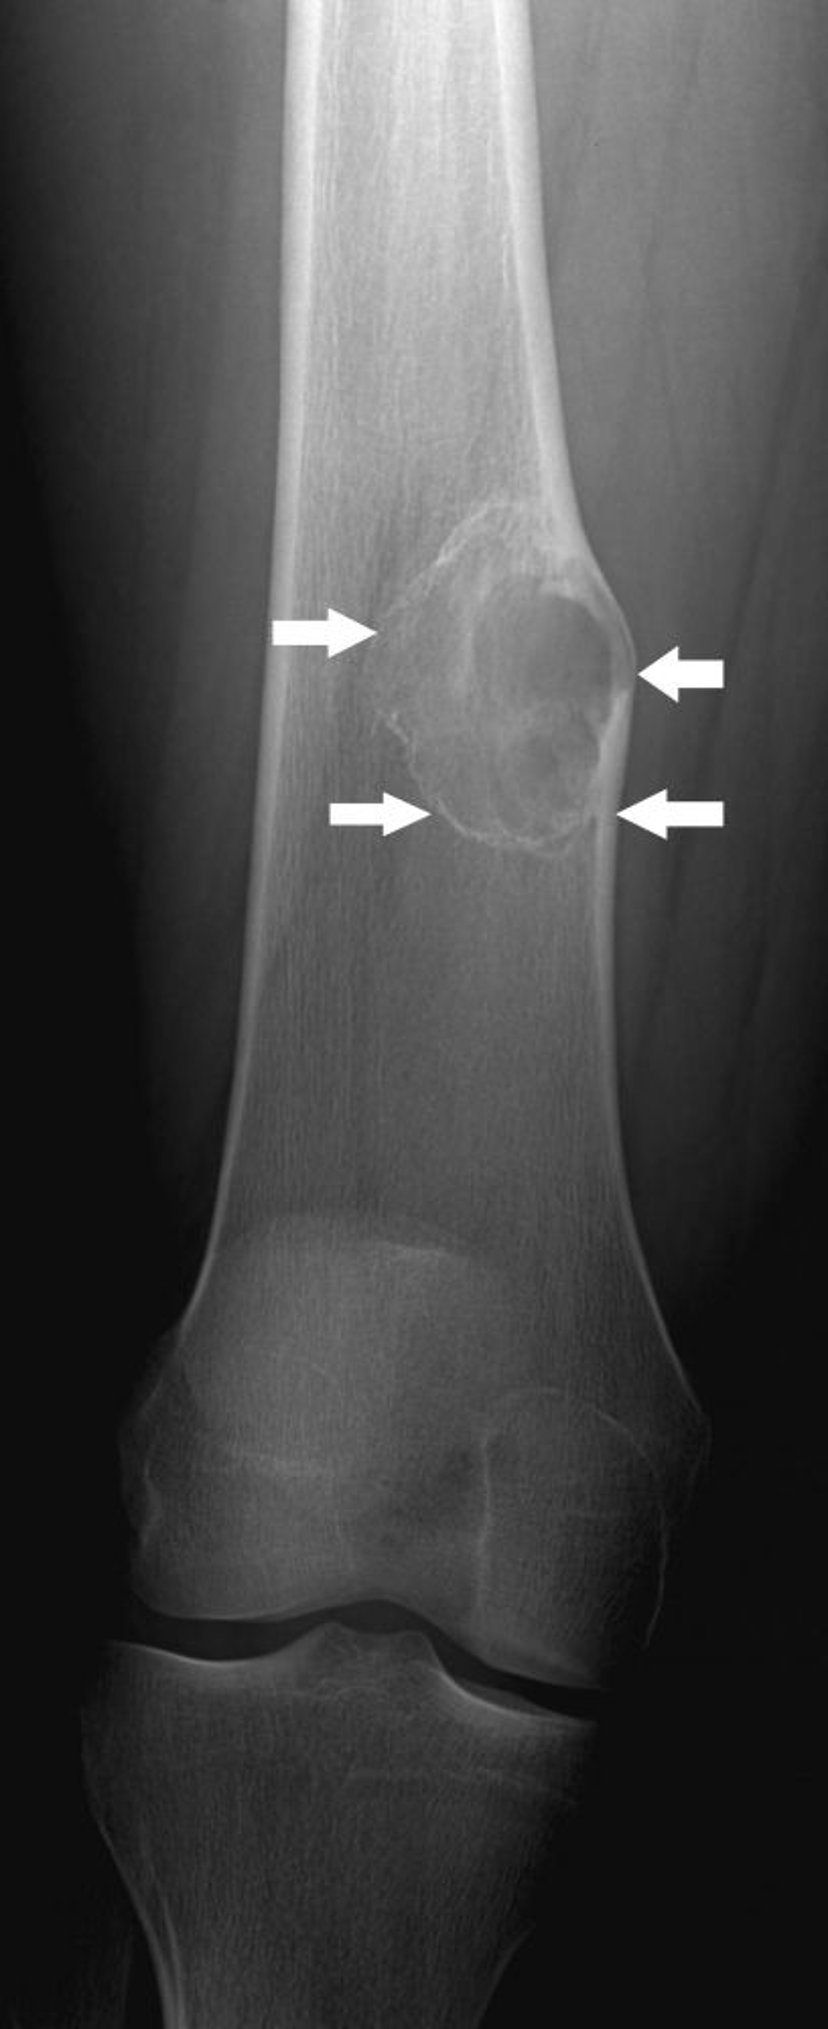

Fibrome non ossifiant

Cette radiographie montre une lésion osseuse (flèches) au-dessus du genou dans le fémur avec une légère expansion, ce qui est typique d'un fibrome non ossifiant.

Image courtoisie de Michael J. Joyce, MD, and Hakan Ilaslan, MD.